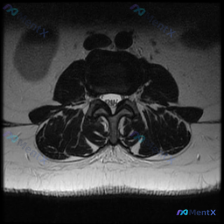

刚整理了一份比较有代表性的腰椎影像读片病例,临床怀疑椎间盘病变,但读片结果有点意思,分享一下思路给大家参考。 病例基本影像信息 这是一张腰椎MRI轴位(横断面)T2加权图像,切面位于腰椎中上段(L2-L3或L3-L4水平),序列特征正常,脑脊液呈高信号,皮质骨及韧带呈低信号,图像质量没有问题。 系统...

看到一份挺有代表性的读片病例,主诉怀疑椎间盘病变,只拿到了单张腰椎MRI轴位T2加权图像,整理一下读片过程和分析思路跟大家讨论。 先看影像基本信息 这是腰椎轴位T2加权像,我们先确认结构:这个序列里脑脊液是亮的高信号,椎间盘髓核是中高信号,骨皮质、黄韧带这些是低信号暗区,刚好能看清楚椎管横截面结构。...